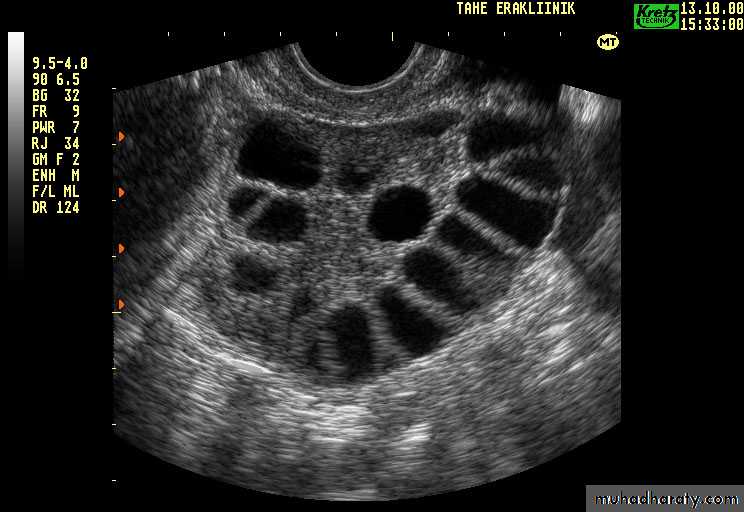

Ultrasound: increased stromal thickness and increasedovarian volume (>10 cm3)(specific for PCOS),and the

presence of 12 or more follicles measured 2-9 mm in

diameter.